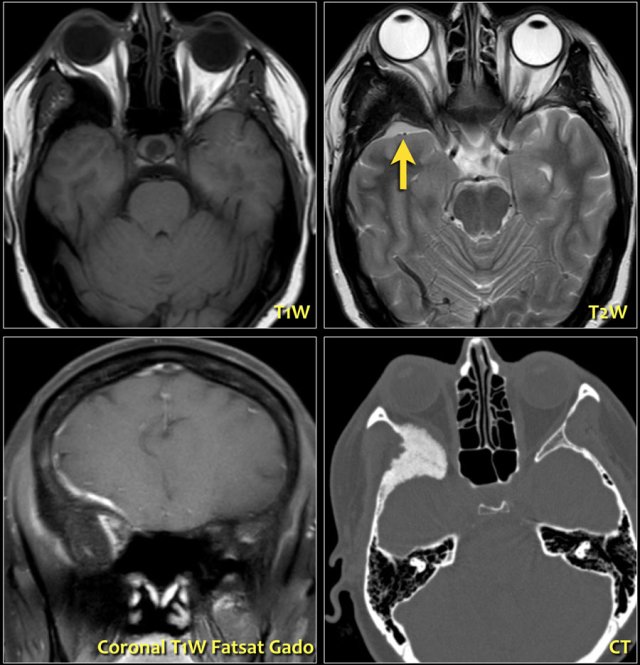

On the left a CT image of a patient with proptosis due to a sphenoid wing lesion.

There are four sphenoid wing lesions that can cause proptosis:

- Sphenoid wing dysplasia

- Fibrous dysplasia

- Paget's disease

- Meningioma with hyperostosis of the sphenoid wing

These images are of a patient who had a slowly progressive proptosis.

On the T2W-image the hyperostosis of the right sphenoid wing is seen, which corresponds to the CT-image.

Notice the small extra-axial lesion (arrow).

This is a meningioma.

On the coronal T1W-image post Gadolineum you can see the enhancement of the meningioma.

When a menigioma grows like this along the neurocranium, it is also called a meningioma en plaque.